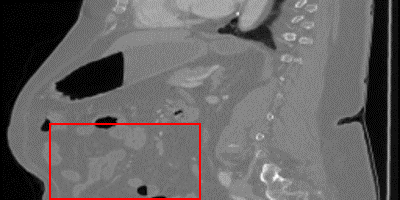

\stackanchorCase 3

\stackanchorHRPSNR/SSIM

\stackanchorDA-VSR37.83/0.978

\stackanchorDA-VSRNAsubscriptDA-VSR𝑁𝐴\textrm{DA-VSR}_{NA}36.68/0.969

\stackanchorSAINT36.77/0.969

\stackanchorSMORE35.08/0.954

\stackanchor3DRDN36.50/0.968

\stackanchor3DRCAN36.42/0.967

\stackanchorBicubic31.62/0.927

Figure 2: Visual comparisons of DA-VSR and other state-of-the-art implementations from the sagittal plane, highlight regions are contrast-adjusted. Case 1 is from the Colon dataset, Case 2 and 3 are from the Kidney dataset[7]. In particular, Case 3 is a lung region cropped from a kidney-containing image. Please refer to the supplemental material for more visual comparisons.

While metrics like PSNR and SSIM are useful to understand performance in aggregate, they can often be too coarse. Domain drift does not happen uniformly on a CT image. Some patches do not suffer as much since similar patches can be observed in the training set, leading to similar overall PSNR metrics; however, some patches suffer heavily due to lack of observations. We provide visualization on SR results, as shown in Fig. 2, to better show where improvements are most often observed. We observe that supervised techniques without adaptation can lead to significant overfitting issues over unseen test sets and create unfaithful details, as seen in Case 2 of Fig. 2 and indicated by the orange arrows. Compared to supervised methods, SMORE produces results that are smoother and more similar to the groundtruth if those patterns are seen in axial slices. For organs that exhibit different patterns between axial and other axes, such as the sagittal spinal structure, SMORE can generate unreliable or overly smooth patterns, as shown in Case 1 of Fig. 2. In comparison, since DA-VSR goes through supervised training on a lung dataset, which contains both LR and HR spine patterns, we observe that it performs much better than SMORE even with adaptation. Interestingly, we also observe improvements over the few unseen cases where a region of lung is included, e.g. in Case 3, by using our proposed adaptation stage. Despite being trained on the lung dataset, other supervised methods still experience local discontinuity over small scale bone structures. In this case, SMORE generates smoother but less structurally reliable details. DA-VSR takes the advantages of both approaches and generate smoother and more reliable details under this challenging case. As no two individuals are the same, DA-VSR’s ability to reduce minor distribution differences can be valuable in real SR applications.